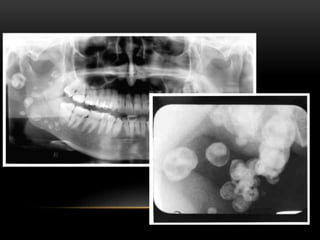

RADIOGRAPHIC FEATURES

• On the panoramic film,

tonsilloliths appear as

single or multiple

radiopacities that overlap

the mid portion of the

mandibular ramus in the

region where the image of

the dorsal surface of the

tongue crosses the ramus

in the palatoglossal air

spaces.

• It appears as clusters of

multiple small ill-

defined radiopacities.

This may vary from 0.5

cm to 14.5 cm in

diameter.

• The radiopacity is of

the same density as

that of cortical bone,

and a little more

radiopaque than

cancellous bone.